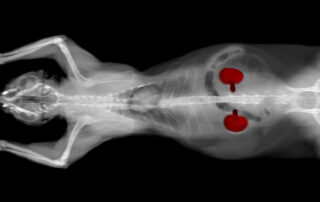

Could Your Pet Have Been Exposed to Rat Poison Without You Realizing It?

Rodent bait is designed to be appealing, and it is, unfortunately, often just as appealing to dogs as it is to the rodents it targets. The tricky thing about most modern rodenticides is that the toxic effects do not appear right away. An anticoagulant rodenticide may take three to five days to produce visible signs of bleeding, by which point [...]